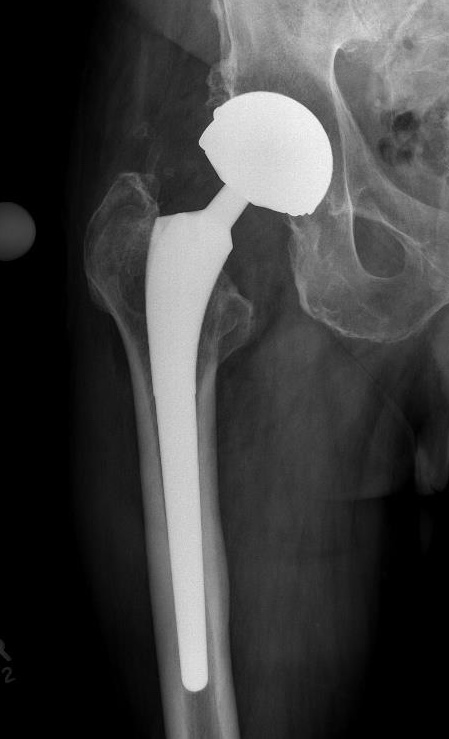

Metal on Metal

Advantage

Large heads

- 30 - 60 mm

- decreases dislocation

- ?improves ROM / function

Disadvantages

1. Increased ion levels

Cobalt and Chromium ions elevated in blood

Creatine cobalt and Creatinine chromium elevated in urine

2. Adverse Local Tissue Reactions

3. High revision rates / Prosthesis recall / Class actions